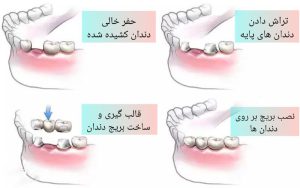

بریج دندان با نام پل دندان نیز شناخته می شود و همانند یک پل، دندان مصنوعی را با دندان های کناری متصل کرده و فضای خالی دندان کشیده شده را پر می کند.در این روش فاصله بین دندان ها پر شده و مشکلات جویدن غذا و زیبایی دندان افراد بر طرف می شود

از رایج ترین انواع بریج دندان نوع سنتی است؛ در این متد از دندان های طرفین استفاده می شود.برای عملی شدن این متد دندان های طرفین تراش داده می شوند تا روکش ها بر روی دندان ها قرار گیرند.دندان بریج که از جنس تمام سرامیک و یا فلز سرامیکی است، به این روکش ها متصل شده و فاصله بین دندان ها به این صورت پر خواهد شد.از نکات مثبت بریج سنتی می توان به عمر و استحکام بالایی که ارائه می دهد اشاره کرد؛ البته برای عملی شدن این متد باید دندان ها تراش داده شوند که این مسئله از معایب بریج سنتی محسوب می شود.

مراحل بریج دندان در کلینیک بزرگمهر

تعداد جلسات بریج به شرایط بیمار بستگی دارد اما به طور کلی بریج دندان در دو و یا نهایتا سه جلسه صورت می گیرد؛ در جلسه اول دندانپزشک بریج های موقت را بررسی کرده، سپس بریجی موقت تا جلسه بعدی برای دهان بیمار قرار داده می شود.

جلسه دوم بریج موقت برداشته شده تا محل آن تمیز و سپس بریج اصلی نصب شود؛ در این جلسه دندانپزشک توصیه هایی در زمینه مراقبتی و جلوگیری از عوارض احتمالی به بیماران خود ارائه خواهد داد.به منظور چکاپ بیشتر وضعیت بریج و دندان های پایه بهتر است تا جلساتی را به معاینه مجدد توسط پزشک خود اختصاص دهید.